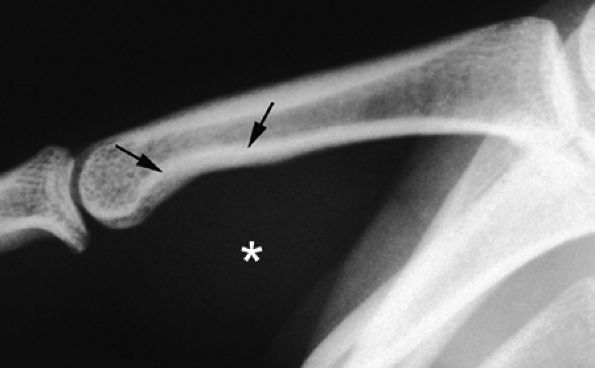

seen with synovial sarcomas. Bone and joint invasion is possible.168 Ultrasonography shows a nonspecific solid mass with a variable color Doppler signal. MR images are specific, depicting a well-defined mass with hemosiderin deposits. Typical signal void artifacts are seen on all sequences, particularly on gradient-echo images, and a more heterogeneous and predominantly low signal is found on T2-weighted images.162,166,169 The lesion typically enhances after intravenous injection of gadolinium (Fig. 11.74). The tendon sheath of the flexor digitorum tendons is usually partially or totally enveloped; the extensor tendons are less commonly involved. Some lesions may be more aggressive, and diffuse lesions are seen in multiple locations with invasion of both the flexor and extensor tendons (Fig. 11.75).170

FIGURE 11.73 ● Giant cell tumor of the tendon sheath. Lateral view radiograph shows a large mass of the palmar soft tissue (asterisk) and bone pressure erosion (arrows).

|